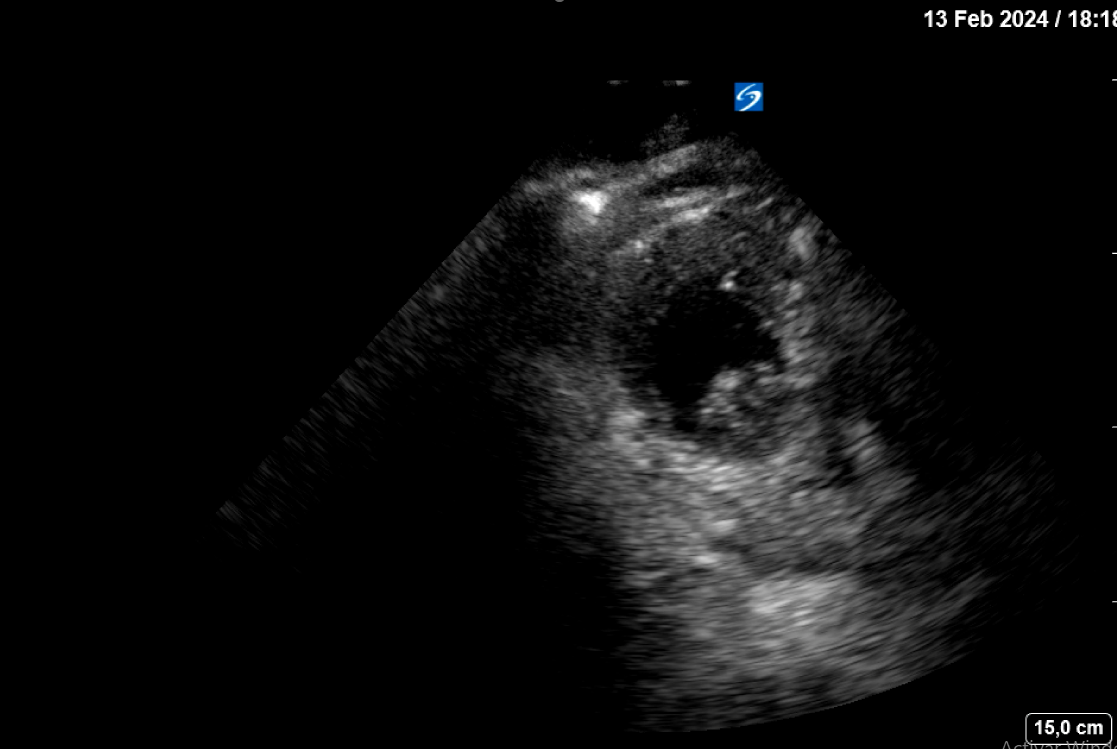

Se realiza interconsulta a Cardiología quien realiza una ecografía clínica cardíaca a pie de cama objetivando acinesia en ápex del ventrículo izquierdo con falta de continuidad a nivel septo-apical con flujo doppler compatible con rotura cardíaca a nivel de ápex que origina un derrame pericárdico moderado-severo, con colapso de ventrículo derecho.

La estabilización hemodinámica junto a los parámetros clínico-ecográficos indican un taponamiento fibrinoso de la rotura cardíaca. Se decide ingreso en planta de medicina interna tras pico de troponina de 7000 pg/mL con el diagnóstico rotura cardíaca contenida. A las 10 horas de la 2ª ecografía clínica y antes de su traslado a una planta médica, se realiza una tercera ecografía clínica dirigida estando el paciente consciente, estable sin dolor. En el mismo se aprecia el mismo derrame pericárdico moderado idéntico al objetivado previamente, pero hay un nuevo hallazgo en el ápex del VI: un trombo intracavitario adherido (imagen 2).